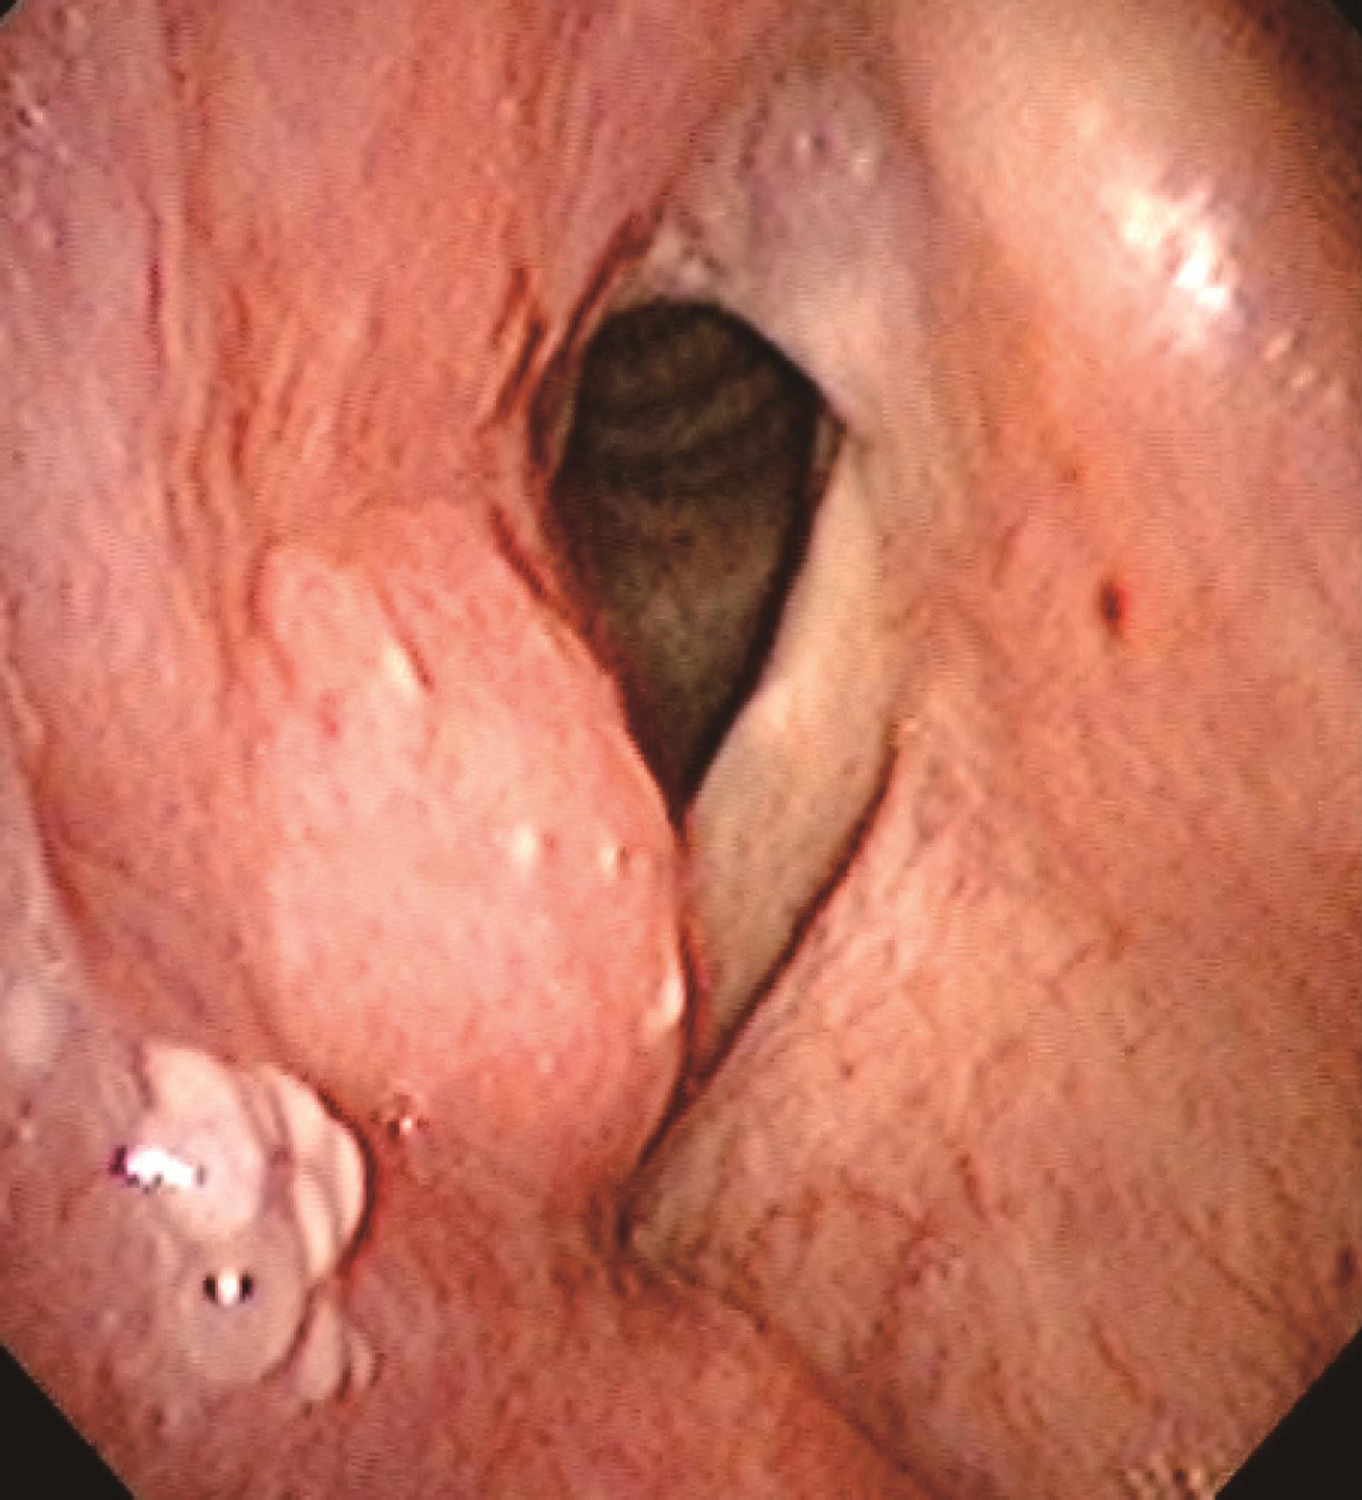

1.2014年1月10日电子喉镜检查

鼻咽部黏膜光滑,未见明显异常。口咽双侧扁桃体无肿大。舌根部淋巴滤泡略增生。右侧梨状窝内侧壁灰白粗糙新生物,形态不规则,累及右侧梨状窝外侧壁、会厌右侧缘和右侧杓会厌皱襞,右侧披裂黏膜及右侧室带肿胀,右侧声带固定,左侧声带活动正常,杓间区及环后区黏膜光滑(图1~图3)。

图3右侧披裂黏膜及右侧室带肿胀,右侧声带固定